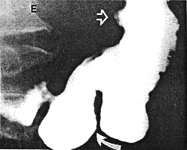

Case 29.2 I.H., 59 year old male, presented with longstanding epigastric pain and malaena. Radiographic examination showed a large ulcer in the posterior wall of the midcorpus. Endoscopic biopsy confirmed the ulcer; the gastric mucosa showed intestinal metaplasia with prominent acute and chronic inflammatory cells, diagnosed as subacute gastritis. No evidence of malignancy was found. After anti-ulcer therapy the patient was temporarily lost to follow-up, but reappeared three years later. Radiographic examination showed the following: after the first two mouthfuls of barium a large ulcer on the posterior wall of the corpus was evident as before (Fig. 29.2A). Before barium entered the duodenum a constant, deep spastic incisura was seen in the pyloric region of the distal greater curvature; swallowing more barium showed it to be due to contraction of the left pyloric loop (Fig. 29.2B). The pyloric sphincteric cylinder between the left loop and the pyloric aperture remained partially contracted, normal cyclical contraction and relaxation being absent. The pyloric aperture remained patent and emptying of fluid barium appeared normal; the appearances were unchanged throughout the examination.

Further treatment followed. Radiographic examination 18 months later showed the ulcer, the prominent contraction of the left pyloric loop and contraction of the remainder of the cylinder to be unchanged (Fig. 29.2C). Endoscopic biopsy confirmed the previous findings. Radiographic examination and endoscopic biopsy after another 5 years showed no change. Billroth II partial gastrectomy confirmed the presence of a large, chronic, benign gastric ulcer on the posterior wall of the corpus; it had penetrated into the pancreas. No organic lesion was seen or felt in the pyloric region.

| Fig. 29.2 A,B. A Case I.H. Large gastric ulcer posterior wall of corpus (open arrow). Deep spastic incisura distal greater curvature (curved arrow). B Case I.H. The spastic incisura is caused by constant contraction of the left pyloric loop (curved arrow). | |

| Fig. 29.2 C-F Case I.H. Eighteen months later the gastric ulcer (open arrow), contraction of the left pyloric loop (curved arrow) and contraction of the sphincteric cylinder are unchanged | |